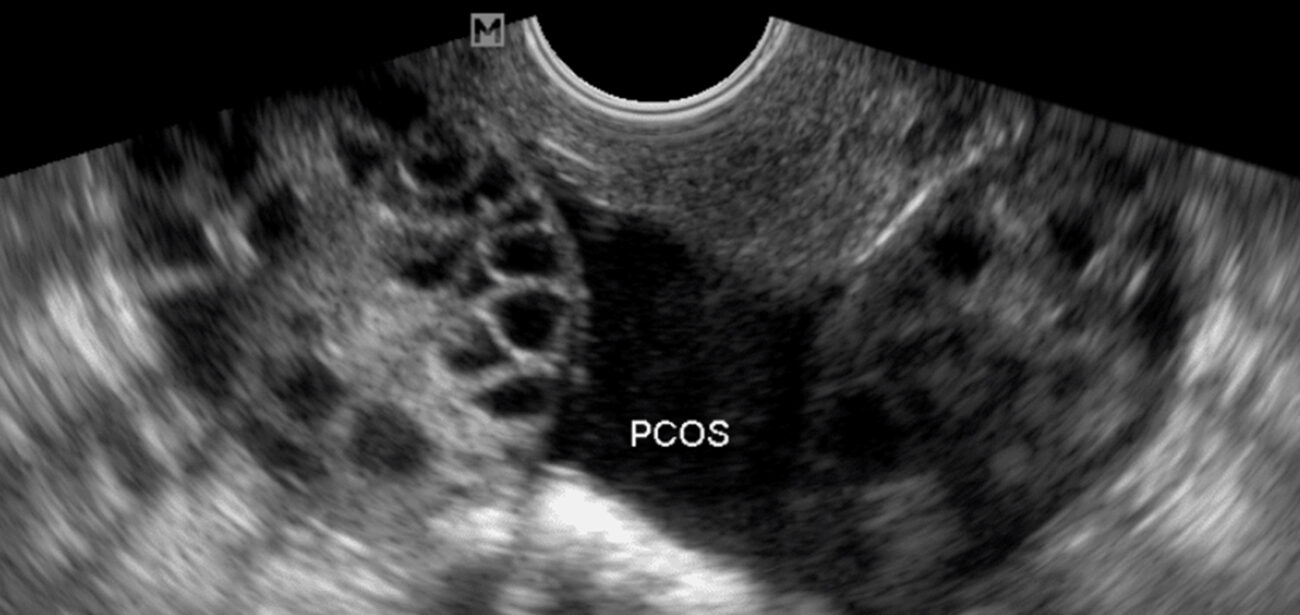

• Ultrason. Bu test, yumurtalıkların boyutuna bakmak ve kistleri olup olmadığını görmek için kullanılır. Ayrıca rahim iç zarının (endometrium) kalınlığına da bakılabilir.